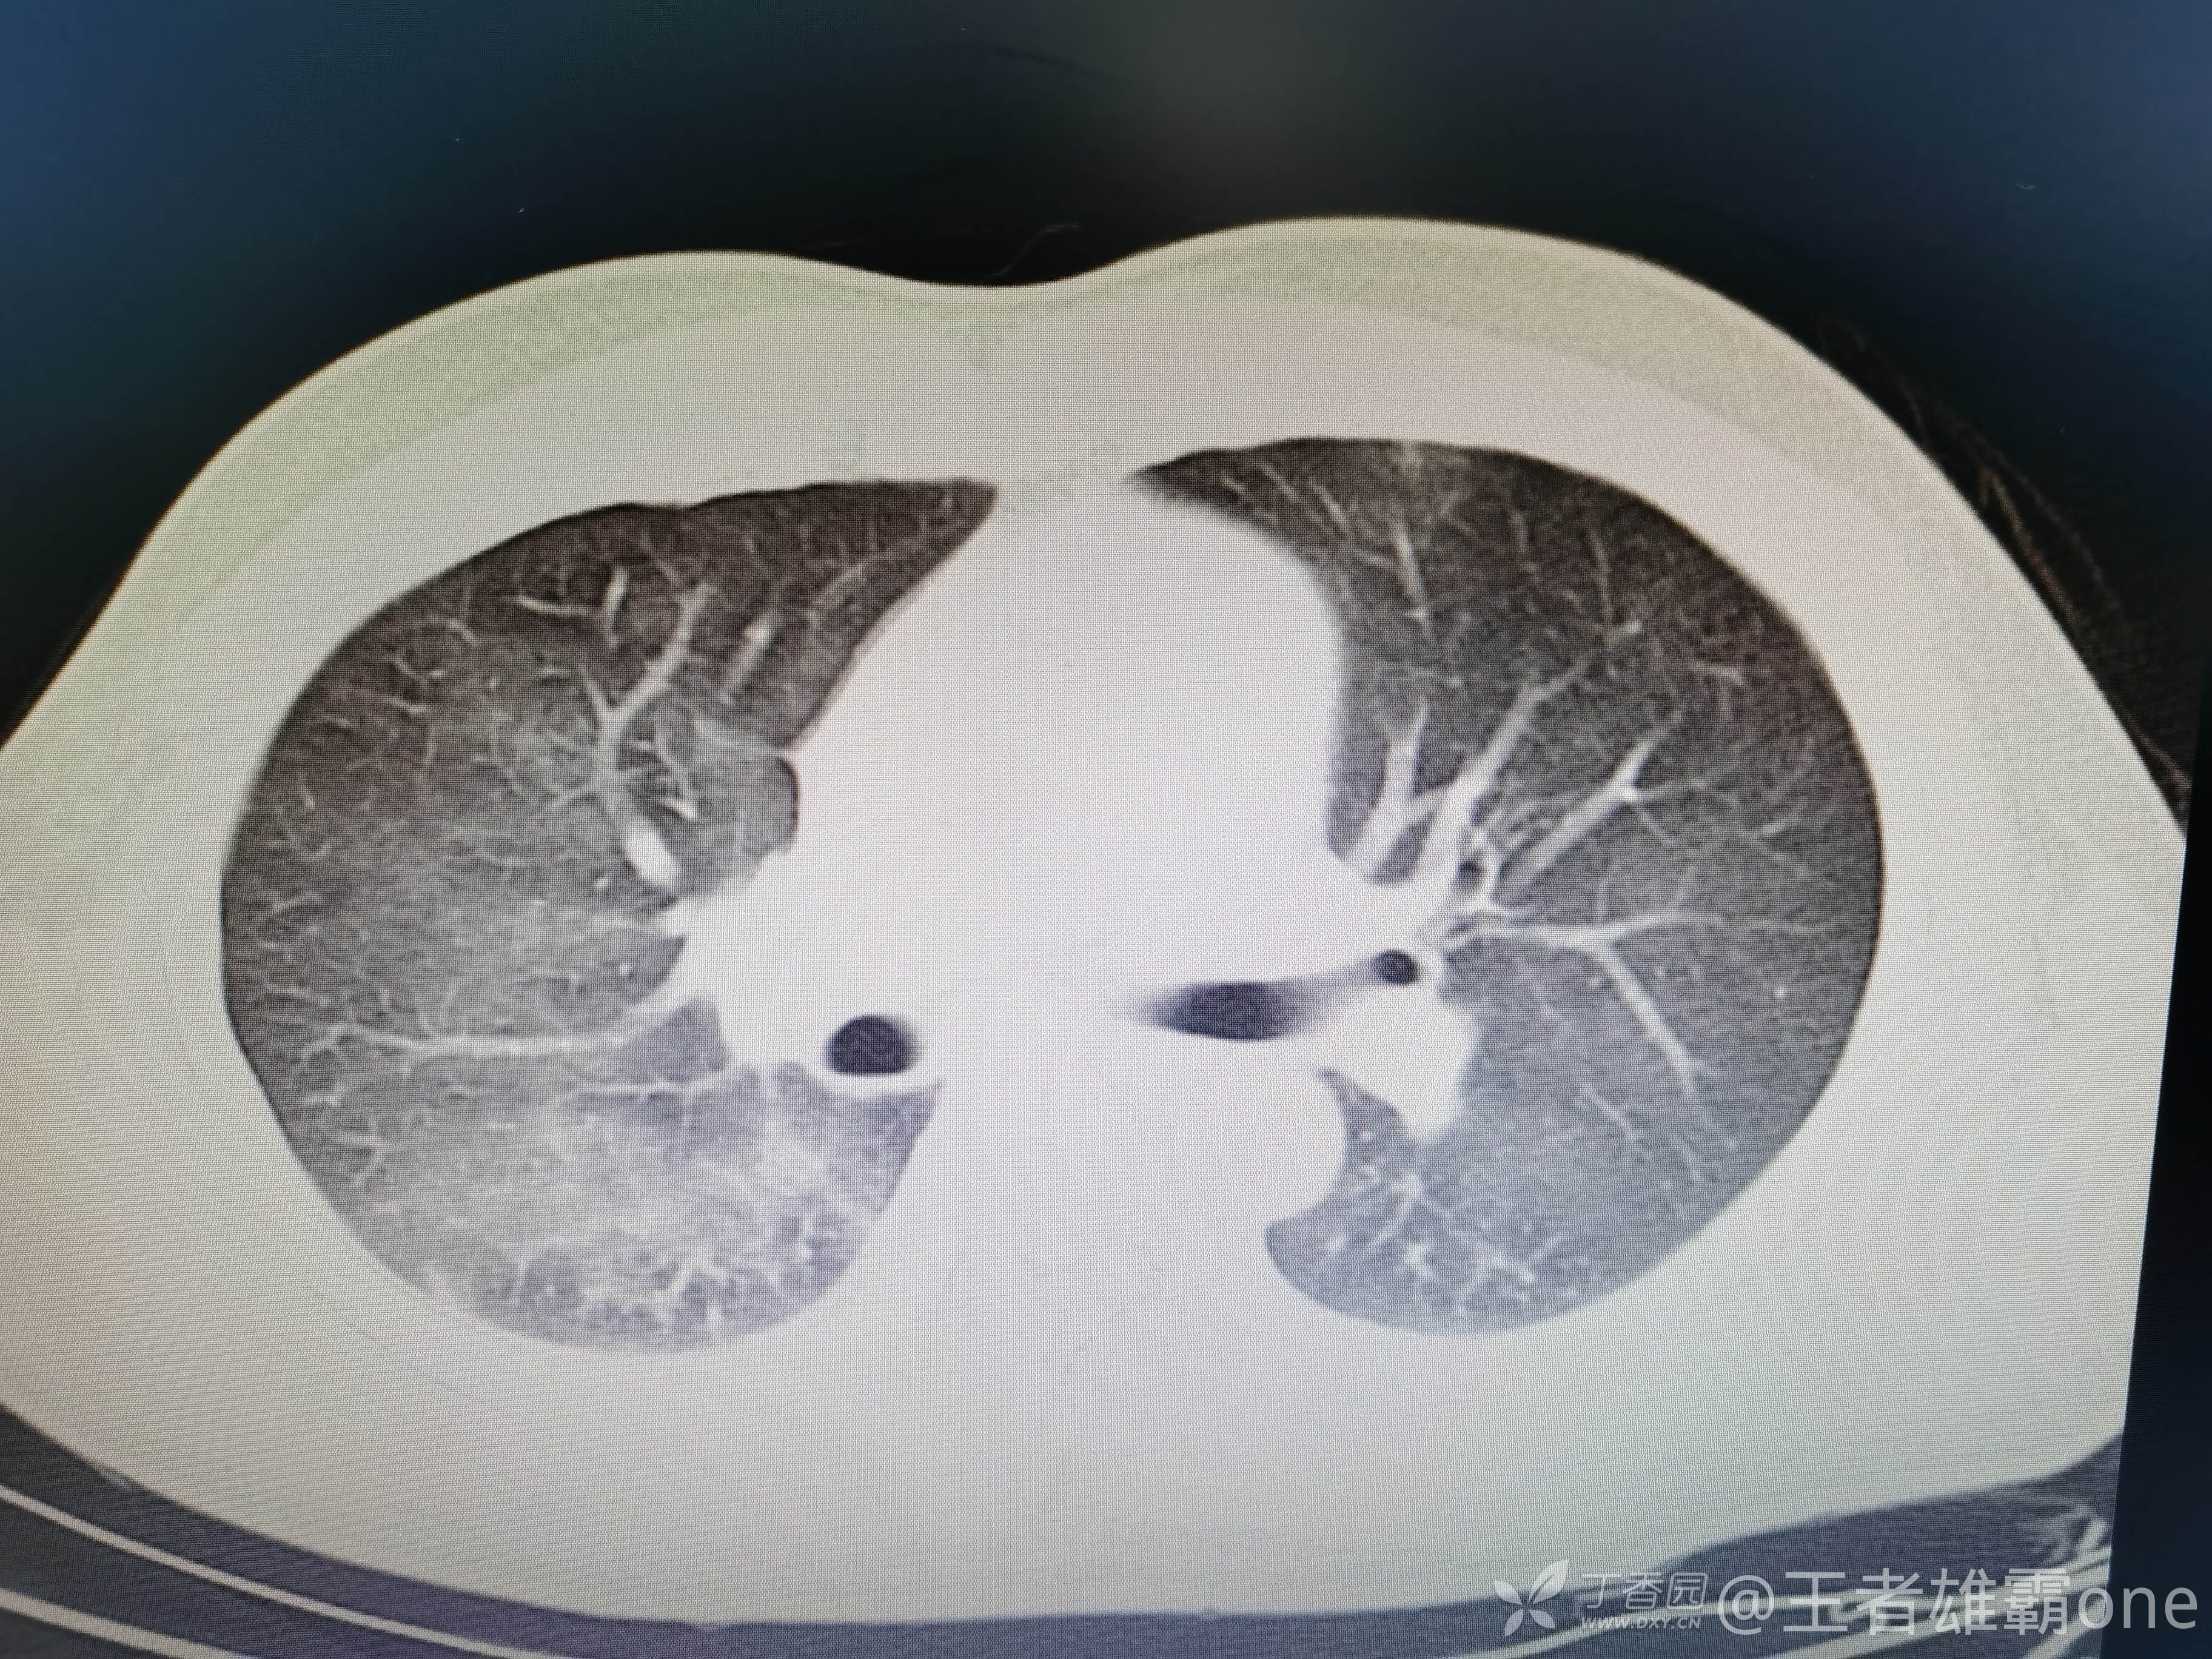

西门开心 推荐男,33岁,否认既往有心脏基础疾病,6-1受伤后急诊行右胫腓骨骨折固定术(术前胸部CT无明显异常,见后面视频前半部分),术后逐渐出现刺激性咳嗽、胸闷,无精神症状,无皮疹,无胸痛,无咯血等。6-6完善胸部CT、脑钠肽前体、心超等辅查,其中脑钠肽前体、心超无明显异常。复查的胸部CT见视频后半部分:

附几张CT图片: